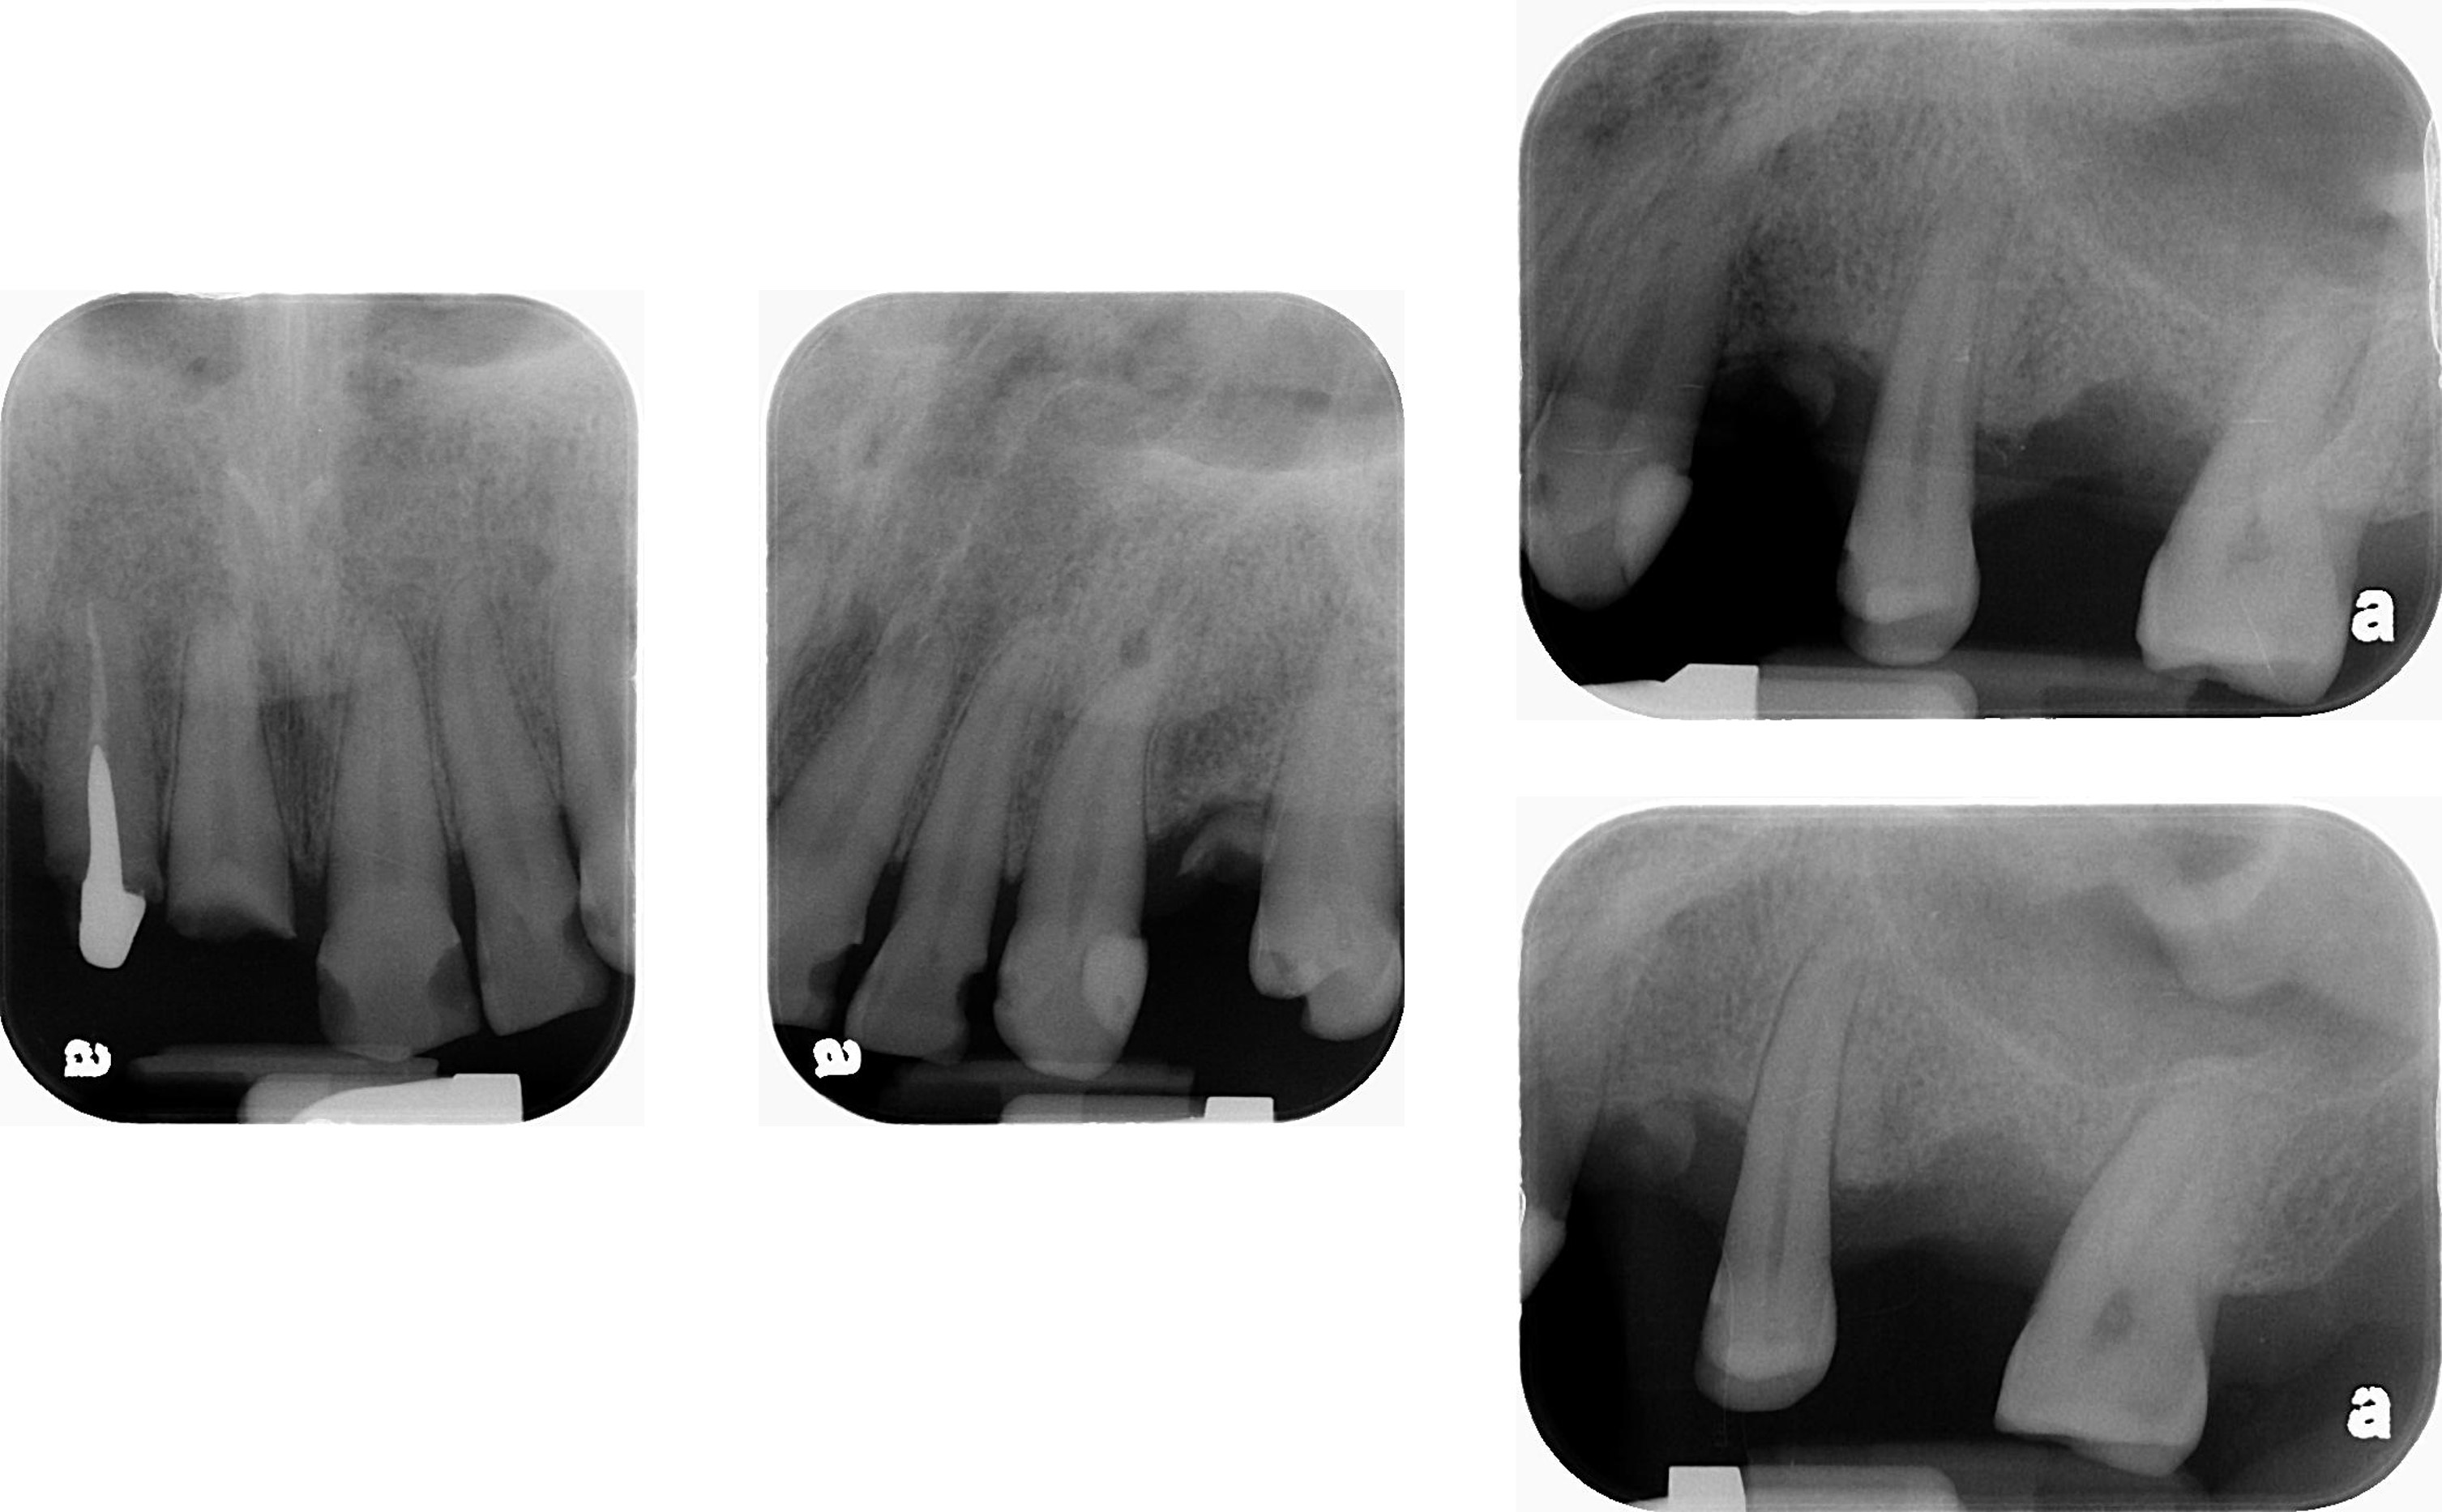

咬合穩定度分析,是評估咬合支撐、運動是否有甘擾,才能了解未來的計畫擬定。

治療前,殘根與牙周支撐不良